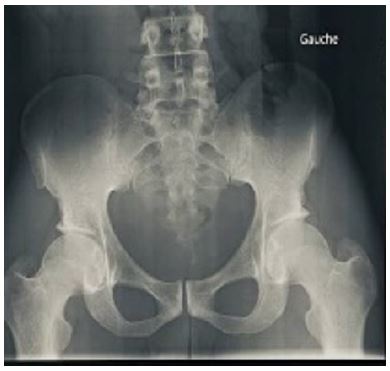

Figure 2: Front pelvic X-ray showing left obturator dislocation.

The vascular and neurological examination was normal, and the rest of the examination was unremarkable. An emergency radiograph of the pelvis showed an anterior obturator dislocation of the left hip (Figure 2).